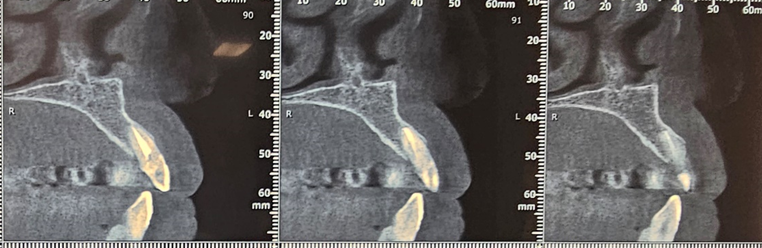

After implant placement (Figure 9), the primary stability of the implant was satisfactory (greater than 35N), the provisional abutment was fixed (Figure 10) and a post-operative retroalveolar radiograph was taken for radiological control of the implant and adaptation of the provisional abutment (Figure 11).

Figure 10. Fixing the temporary abutment to the implant

Figure 11. Postoperative retroalveolar radiography

PMMA resin was placed around the provisional abutment, and the occlusion was checked to ensure that the provisional prosthesis was underbite (Figure12).

Figure 9. Drilling sequence

Figure 12. Placement of PMMA resin and final result of provisional prosthesis